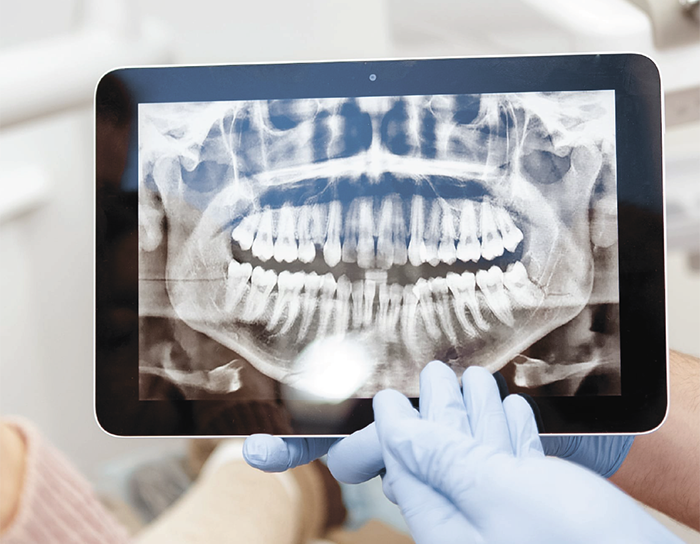

Планирование лечения зубов и его проведение сегодня не обходится без рентгенологических методов диагностики – прицельного снимка зуба, панорамного снимка зубочелюстной системы (ортопантомограммы) и компьютерной томографии. И сегодня мы хотим поговорить с Вами о панорамном снимке. Именно такое исследованиедля большинства стоматологов является «золотым стандартом» при «знакомстве» с пациентом – он необходим и для терапевта, и для хирурга, и для ортодонта.«Зачем же нужен панорамный снимок зубов? Где его можно сделать и сколько это будет стоить?» – это самые часто задаваемые вопросы пациентами, на которые мы хотим ответить в этой статье.Еще раз о том, что такое панорамный снимок зубов

Панорама (ортопантомограмма, ОПТГ, панорамный снимок челюстей) – это обзорный круговой снимок зубов, при котором видна вся челюсть, развернутая в двухмерной плоскости. Она может быть цифровой и пленочной.

На начальном этапе оценки состояния полости рта стоматолог обязательно назначает панорамный рентген-снимок.

Панорамный снимок (или ортопантомограмма) – это плоское двухмерное изображение челюстей, зубов, гайморовых пазух и даже височно-нижнечелюстного сустава. Поскольку поверхность челюстей изогнутая, на плоской рентгеновской плёнке снимок отображается неравномерно увеличенным в боковых и передних отделах челюстей – то есть слегка деформированым.